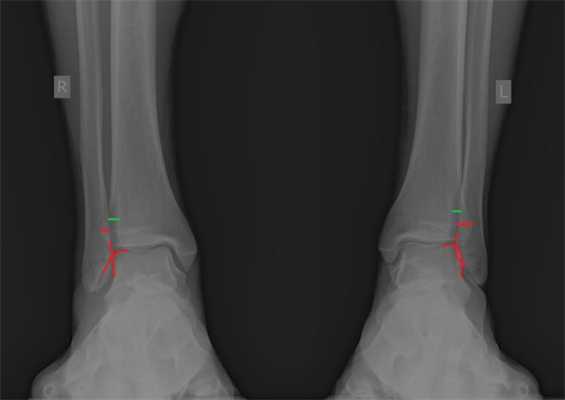

При детальном изучении снимков определяется увеличение межберцовой щели до 7,5 мм, уменьшения зоны перекрытия большеберцовой и малоберцовой костей до 5 мм, отсутствие на стороне поражения перекрытия тени таранной кости и малоберцовой кости.

На рентгенограмме костей правого и левого голеностопных суставов в прямой проекциии, снимки стоя - справа определяются признаки повреждения дистального межберцового синдесмоза - степень взаимного перекрытия берцовых костей 5мм (в норме больше 6мм) увеличенное большеберцовое - малоберцовое пространство - 7.5мм (в норме до 6мм).

При выполнении стресс рентгенограмм определяется выраженная латеральная нестабильность голеностопного сустава.

Для подтверждения механической нестабильности выполнены стресс-рентгенограммы голеностопного сустава с «варус-стресс тестом» и «тестом переднего выдвижного ящика». Критериями для постановки диагноза нестабильности является ангуляция таранной кости в коронарной плоскости более 4 градусов и смещение таранной кости кпереди в сагиттальной плоскости на 4 мм, или разница с контрлатеральной стороной в 2 градуса и 2 мм соответственно.

Если с варус-стресс тестом всё очень наглядно, оценивать передний выдвижной ящик рентгенологически чуть сложнее. Для этого можно либо обозначить центр купола таранной кости и встречной суставной поверхности большеберцовой кости точками и сравнивать расстояние между ними с или без нагрузки в задне-переднем направлении, либо использовать в качестве вспомогательного ориентира тень медиальной лодыжки и расстояние от неё до начала шейки таранной кости.